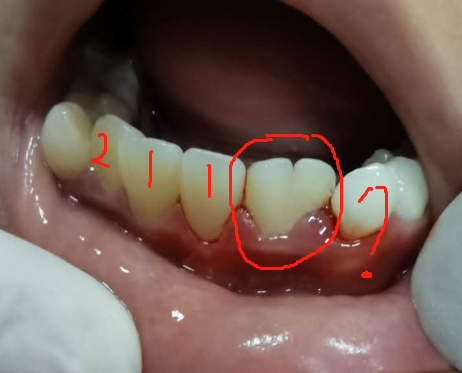

(下图是融合牙,这算两颗牙齿还是一颗牙齿?)

(上图为先天缺失两颗牙齿)